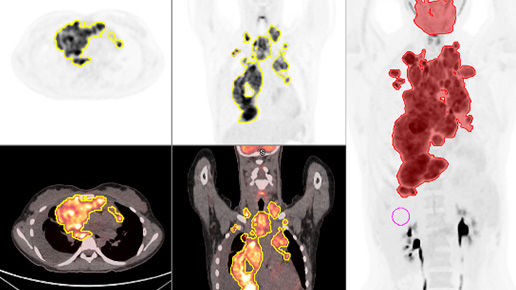

Advanced reconstruction

Precision DL achieves superb image quality with better contrast-to-noise ratio and contrast recovery⁶

Reconstruction is supported by full convergence BSREM together with Precision DL. The high-quality images, acquired with 405 cps NEMA sensitivity and exceptionally high spatial resolution by dBGO detectors, can be further processed by Precision DL AI-aided processing.⁴